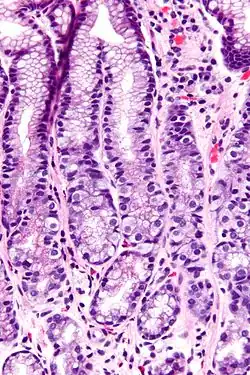

Micrograph of the gastric antrum showing abundant fried egg-like G cells. H&E stain.

G cells have a distinctive microscopic appearance that allows one to separate them from other cells in the gastric antrum; their nuclei are centrally located in the cell. They are found in the middle portion of the gastric glands.